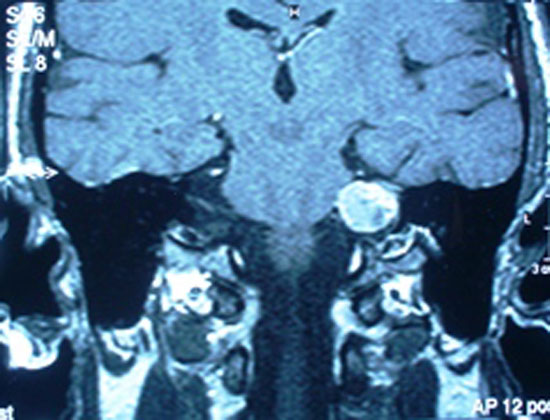

Paciente do sexo masculino, 56 anos, inaugurou história clínica com hipoacusia leve em ouvido direito e severa em ouvido esquerdo, revelada

em audiometria, realizou também ressonância nuclear magnética, cujo resultado revelou processo expansivo, em ângulo pontocerebelar

esquerdo, com continuidade com o conduto auditivo interno adjacente, medindo aproximadamente 2,5 x 2,0 x 1,6cm, sendo sugestivo de

neurinoma do acústico. Sua sintomatologia referida era cefaléia intermitente em região retro auricular e hipoacusia com evolução de

RNM do Crânio (mastóides)

Processo expansivo, localizado no ângulo pontocerebelar esquerdo, apresentando continuidade com o conduto auditivo interno adjacente, medindo aproximadamente 2,5 x 2,0 x 1,6cm nos seus maiores diâmetros.